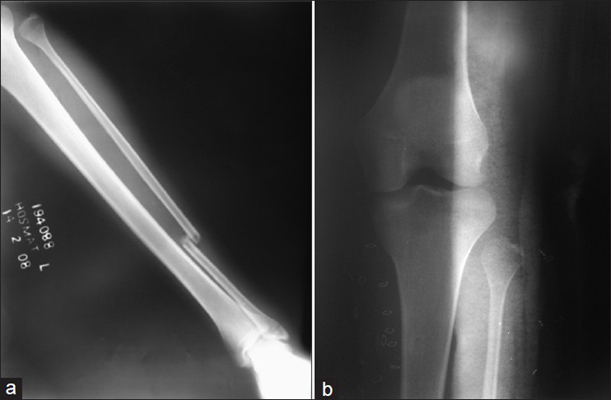

骨折圖片

骨裂